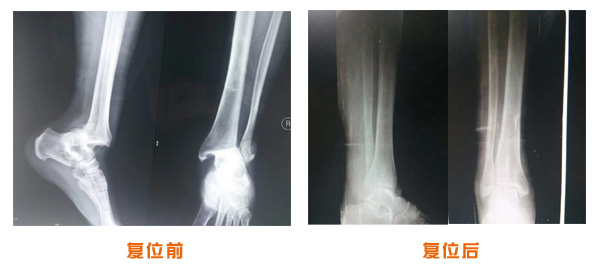

尺橈骨克雷氏骨折治療前后